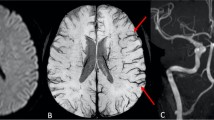

SWI showed more numerous veins and/ or conspicuous large veins over the side of affection in more than half of the studied subjects (ten patients). Seven patients showed no significant difference in appearance in both the cerebral hemispheres, and in one patient, the observed veins were less in the affected hemisphere. More than half of the patients (66%) with carotid occlusion showed conspicuous veins over the ipsilateral cerebral hemisphere (Figs 1 and 2). None of the patients in the stenosis group demonstrated this finding. The two venous signs (more numerous veins and/or conspicuous large veins) evaluated for in this study were observed together in most of the patients who manifested SWI abnormalities (nine of ten patients).When visualized, veins were not restricted to the arterial territories and extended beyond the vascular boundaries.

a–f Case 17: FLAIR axial image (a) shows lacunar infarcts in bilateral centrum semiovale (CSO) and subacute infarcts in the left frontal and temporoparietal region. MRA demonstrates complete occlusion of left ICA from its origin (b). SWI axial images (c through f) demonstrate prominent veins over the left cerebral hemisphere. Note increased mineral deposition in both basal ganglia